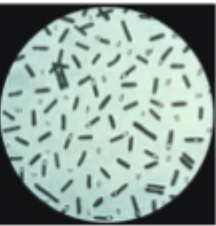

features of Clostridium bacteria

gram-positive, anaerobic, produce spores